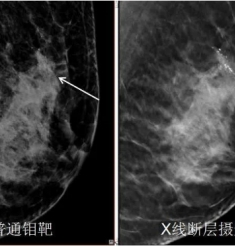

肿瘤科副主任戴堂知介绍,VMAT是在图像引导放射治疗技术(IGRT)基础上成功研发,集新型高精尖加速器与逆向优化治疗计划设计软件、精密三维和两维的剂量验证设备于一身。该项技术可满足全身各部位肿瘤治疗的需要,更适合早期癌症的治疗。

由于在放射治疗过程中,可以清晰地“看”到肿瘤的情况,这一技术又被称为“所见即所治”技术。通过图像引导放射治疗的应用,能在确保肿瘤得到充分照射的前提下,更好地保护正常组织。VMAT可以让医生在同一参考系下为患者进行定位和治疗,确保使周围正常组织的损伤降到最低的条件下进一步加强对肿瘤的治疗,极大地提高了普通调强放射治疗的可信度。

戴堂知表示, 作为目前国际最先进的放射治疗技术,VMAT以其“快、准、优”的特定为肿瘤放射治疗病人提供更全面、科学、精准的技术解决方案。VMAT治疗技术从IMRT调强治疗的10-20分钟,大幅度缩短到2-6分钟,减少病人在治疗过程中的不自主运动几率,提高治疗精度。(如鼻咽癌IMRT每次需要10-15分钟,此技术仅需5分钟左右);VMAT治疗技术可在360度多弧设定任何角度范围内可旋转照射,多个方向上对肿瘤进行照射,不但可从前后、左右方向,还可以从上下方向任何角度对肿瘤进行照射,比“γ-刀”照射范围更大,更灵活,更精准,它不仅做到三维空间顺形治疗,还能调整控制放射线在肿瘤上的强度及在每次治疗时可立即取得三维电脑断层扫描影像做超精确的治疗定位;VMAT治疗技术不仅让放射线随着肿瘤厚度调弱、增强,还能考虑肿瘤体积各部位的厚度不同,来给予最适合的射线强度,同时避开躲藏在肿瘤中间或凹陷处的重要器官,增加肿瘤控制率和降低正常组织并发症的机率,减少治疗后的副作用。以正常组织超低剂量投照,获得肿瘤治疗区的最大剂量覆盖,从而取得最优化的剂量分布效果。